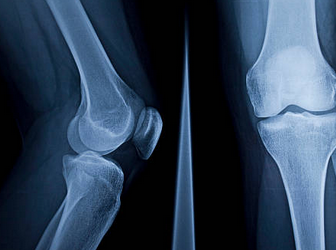

무릎 연골 찢어짐 증상 원인 치료방법 수술비용 등 총 정리해드리도록 하겠습니다. 무릎 연골 찢어짐은 무릎 관절에 있는 연골이 부상이나 나이로 인해 손상되는 경우를 말합니다. 연골은 뼈와 뼈 사이에 있는 연한 조직으로, 뼈의 마찰을 줄여주고 충격을 흡수하는 역할을 합니다.

무릎 연골 찢어짐 정보